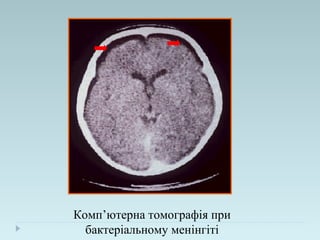

Комп’ютерна томографія при

бактеріальному менінгіті